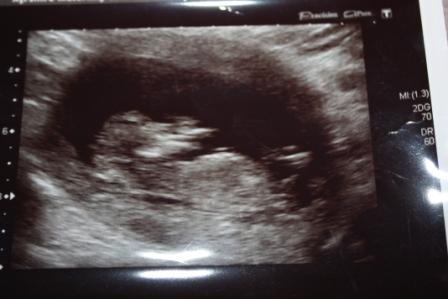

Gender scan update!

I know photos aren't the best! Not sure if nub is even visible at all, sure the thing pointing up must be cord as its as big as baby's forearm LOL!! :wink:

Sonographer put me at 12w6d but I reckon more like 12w1d.

Any guesses welcome!! :happy:

Attachment 5675